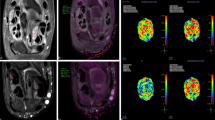

Evaluation protocol and DITI interpretation

The IRIS-8000® (Medicore, Seoul, Korea) was used to obtain the thermographic image. DITI was performed before electrodiagnosis with the following conditions: the indoor temperature was maintained at 23–25 °C; the subject was dressed in loose clothing and allowed to acclimatize to the room temperature for 15‒20 min; the distance from the body to the thermographic camera was 1.5 m; lotion or ointment was not applied before the test; all metal accessories, splints, and topical patches were removed; vigorous exercise and physical therapy within 4 h of the test were avoided; and alcohol and caffeine consumption and smoking were prohibited within 12 h before the examination.

Because previous studies reported that median-innervated somatosensory and vasomotor territories are similar in the palm area26, 27, we designated six regions of interest of the thermal image of the palm side. Skin temperature was measured at the center of the finger pulp of the first, second, third, and fifth digits based on an area of 400 data points. Additionally, measurements were obtained from the thenar eminence and hypothenar eminence based on an area of 800 data points (Fig. 2). The mean value of all data points in the region of interest was calculated. The final result is displayed in degrees (Celsius) by converting the validated red–green–blue data to temperature. For data interpretation and quantitative analyses, we defined the following indicators and calculated the values by substituting the average body temperature measured within each region of interest9: